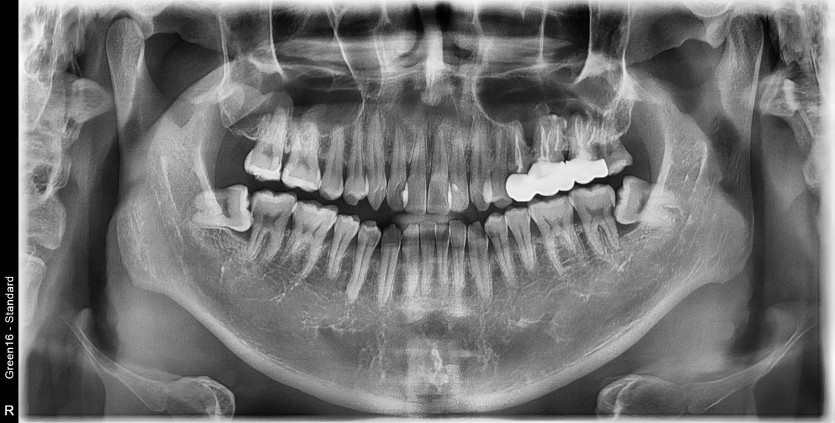

#28,38,48 사랑니 발치

구강 외과 전문의가 당일 발치했습니다.